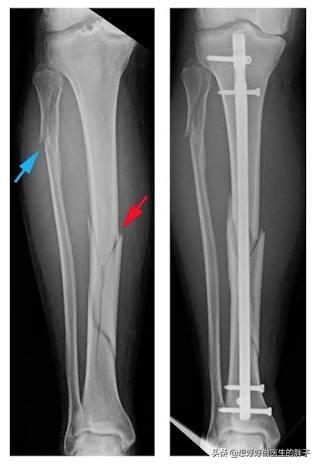

小腿有两根重要的骨头,一根是胫骨,一根是腓骨,小腿骨折根据骨骼损伤的位置可以分为胫骨骨折、腓骨骨折或者胫腓骨双折;而不同骨折又可以分为多种骨折方式,比如闭合骨折、开放骨折、螺旋骨折、粉碎骨折等等,这又可以分为是否存在血管损伤、是否有筋膜室综合征等并发症,所以简单谈论小腿骨折以后如何快速恢复有些复杂,所以我们将小腿骨折设置为:小腿胫腓骨双折、钢板内固定术后,如何能恢复的安全、快速呢?这样会更好的帮助大家理解骨折的基本注意事项,和如何康复,何时康复更好!